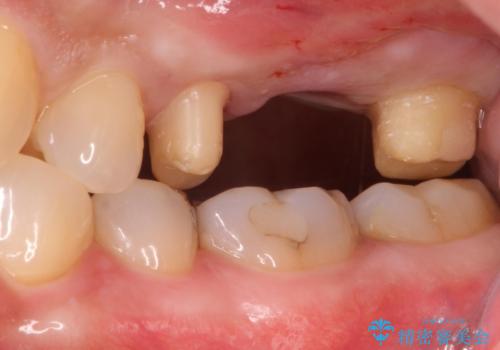

ブリッジでの修復は、抜歯後に歯がなくて噛みにくい期間が一切ありません。

歯茎の状態も良く、適合の良いブリッジを装着することができました。

- 左上567:仮歯11,000円×3本、ジルコニアクラウン(スタンダード):121,000円×3本 合計396,000円費用は治療当時の料金となります